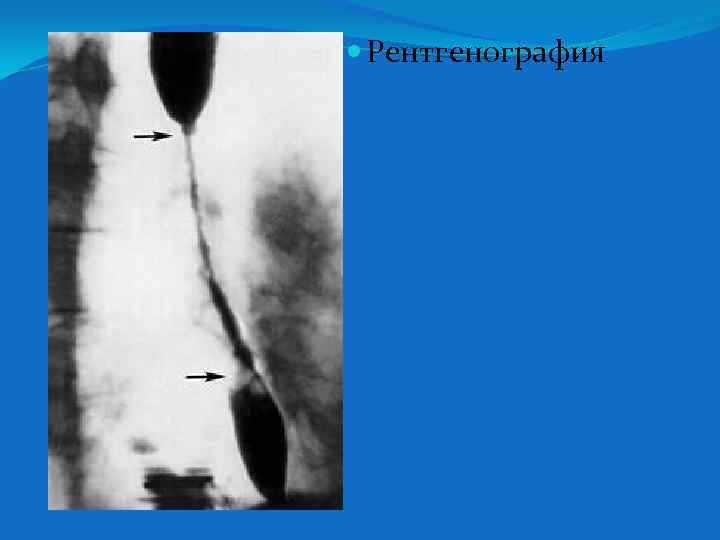

Рентгенография

Контрастная R- графия пищевода - при исследовании пищевода отмечается его значительное сужение на протяжении средней и нижней трети, стенки ровные, перистальтика усилена. Учитывая результаты R- графии пищевода ФГДС проводить не стали.